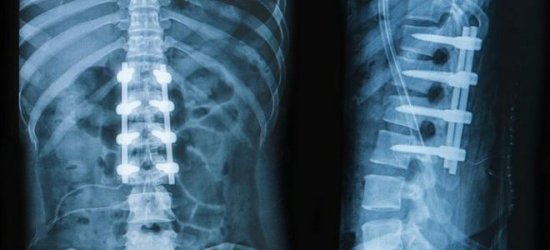

Почему болит низ спины, может установить только врач. Ни в коем случае не следует заниматься самодиагностикой и самолечением. Диагноз ставится на основании жалоб больного, клинических проявлений, анамнестических данных, результатов инструментальных методов исследования. Пациенту назначают рентгенографию, миелографию, МРТ, КТ и другие виды обследований.

Компьютерная томография является эффективным и высокоинформативным способом выявления различных структурных изменений в позвоночнике, вызванных травматизацией, инфекционным процессом, опухолевыми образованиями, остеопорозом и другими заболеваниями. В основе миелографии лежит применение контрастирующего вещества. Метод применяют при подозрении на стеноз позвоночного канала, грыжевых образованиях, опухолях и других патологических процессах в позвоночнике.

Неотъемлемая составляющая диагностики болей в спине – инструментальные исследования